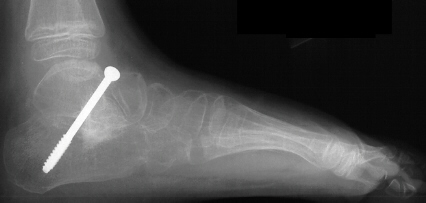

Due to persistent foot pain and excessive callus formation over the

medial arch the patient was taken to the OR and underwent surgical treatment

of the left foot. The procedure consisted of :

- subtalar arthrodesis with autograft bone graft and screw fixation

- closing wedge calcaneocuboid arthrodesis with open pinning

- reduction and open pinning of the talonavicular joint

- midfoot soft tissue release of the talonavicular, calcaneocuboid and

subtalar joints

Post operatively, the patient was placed in a long leg cast. Preliminary

results show satisfactory reduction of the talonavicular joint, correction

of hindfoot valgus, dorsiflexion of the talus on the calcaneus, and correction

of forefoot adduction immediately post op.